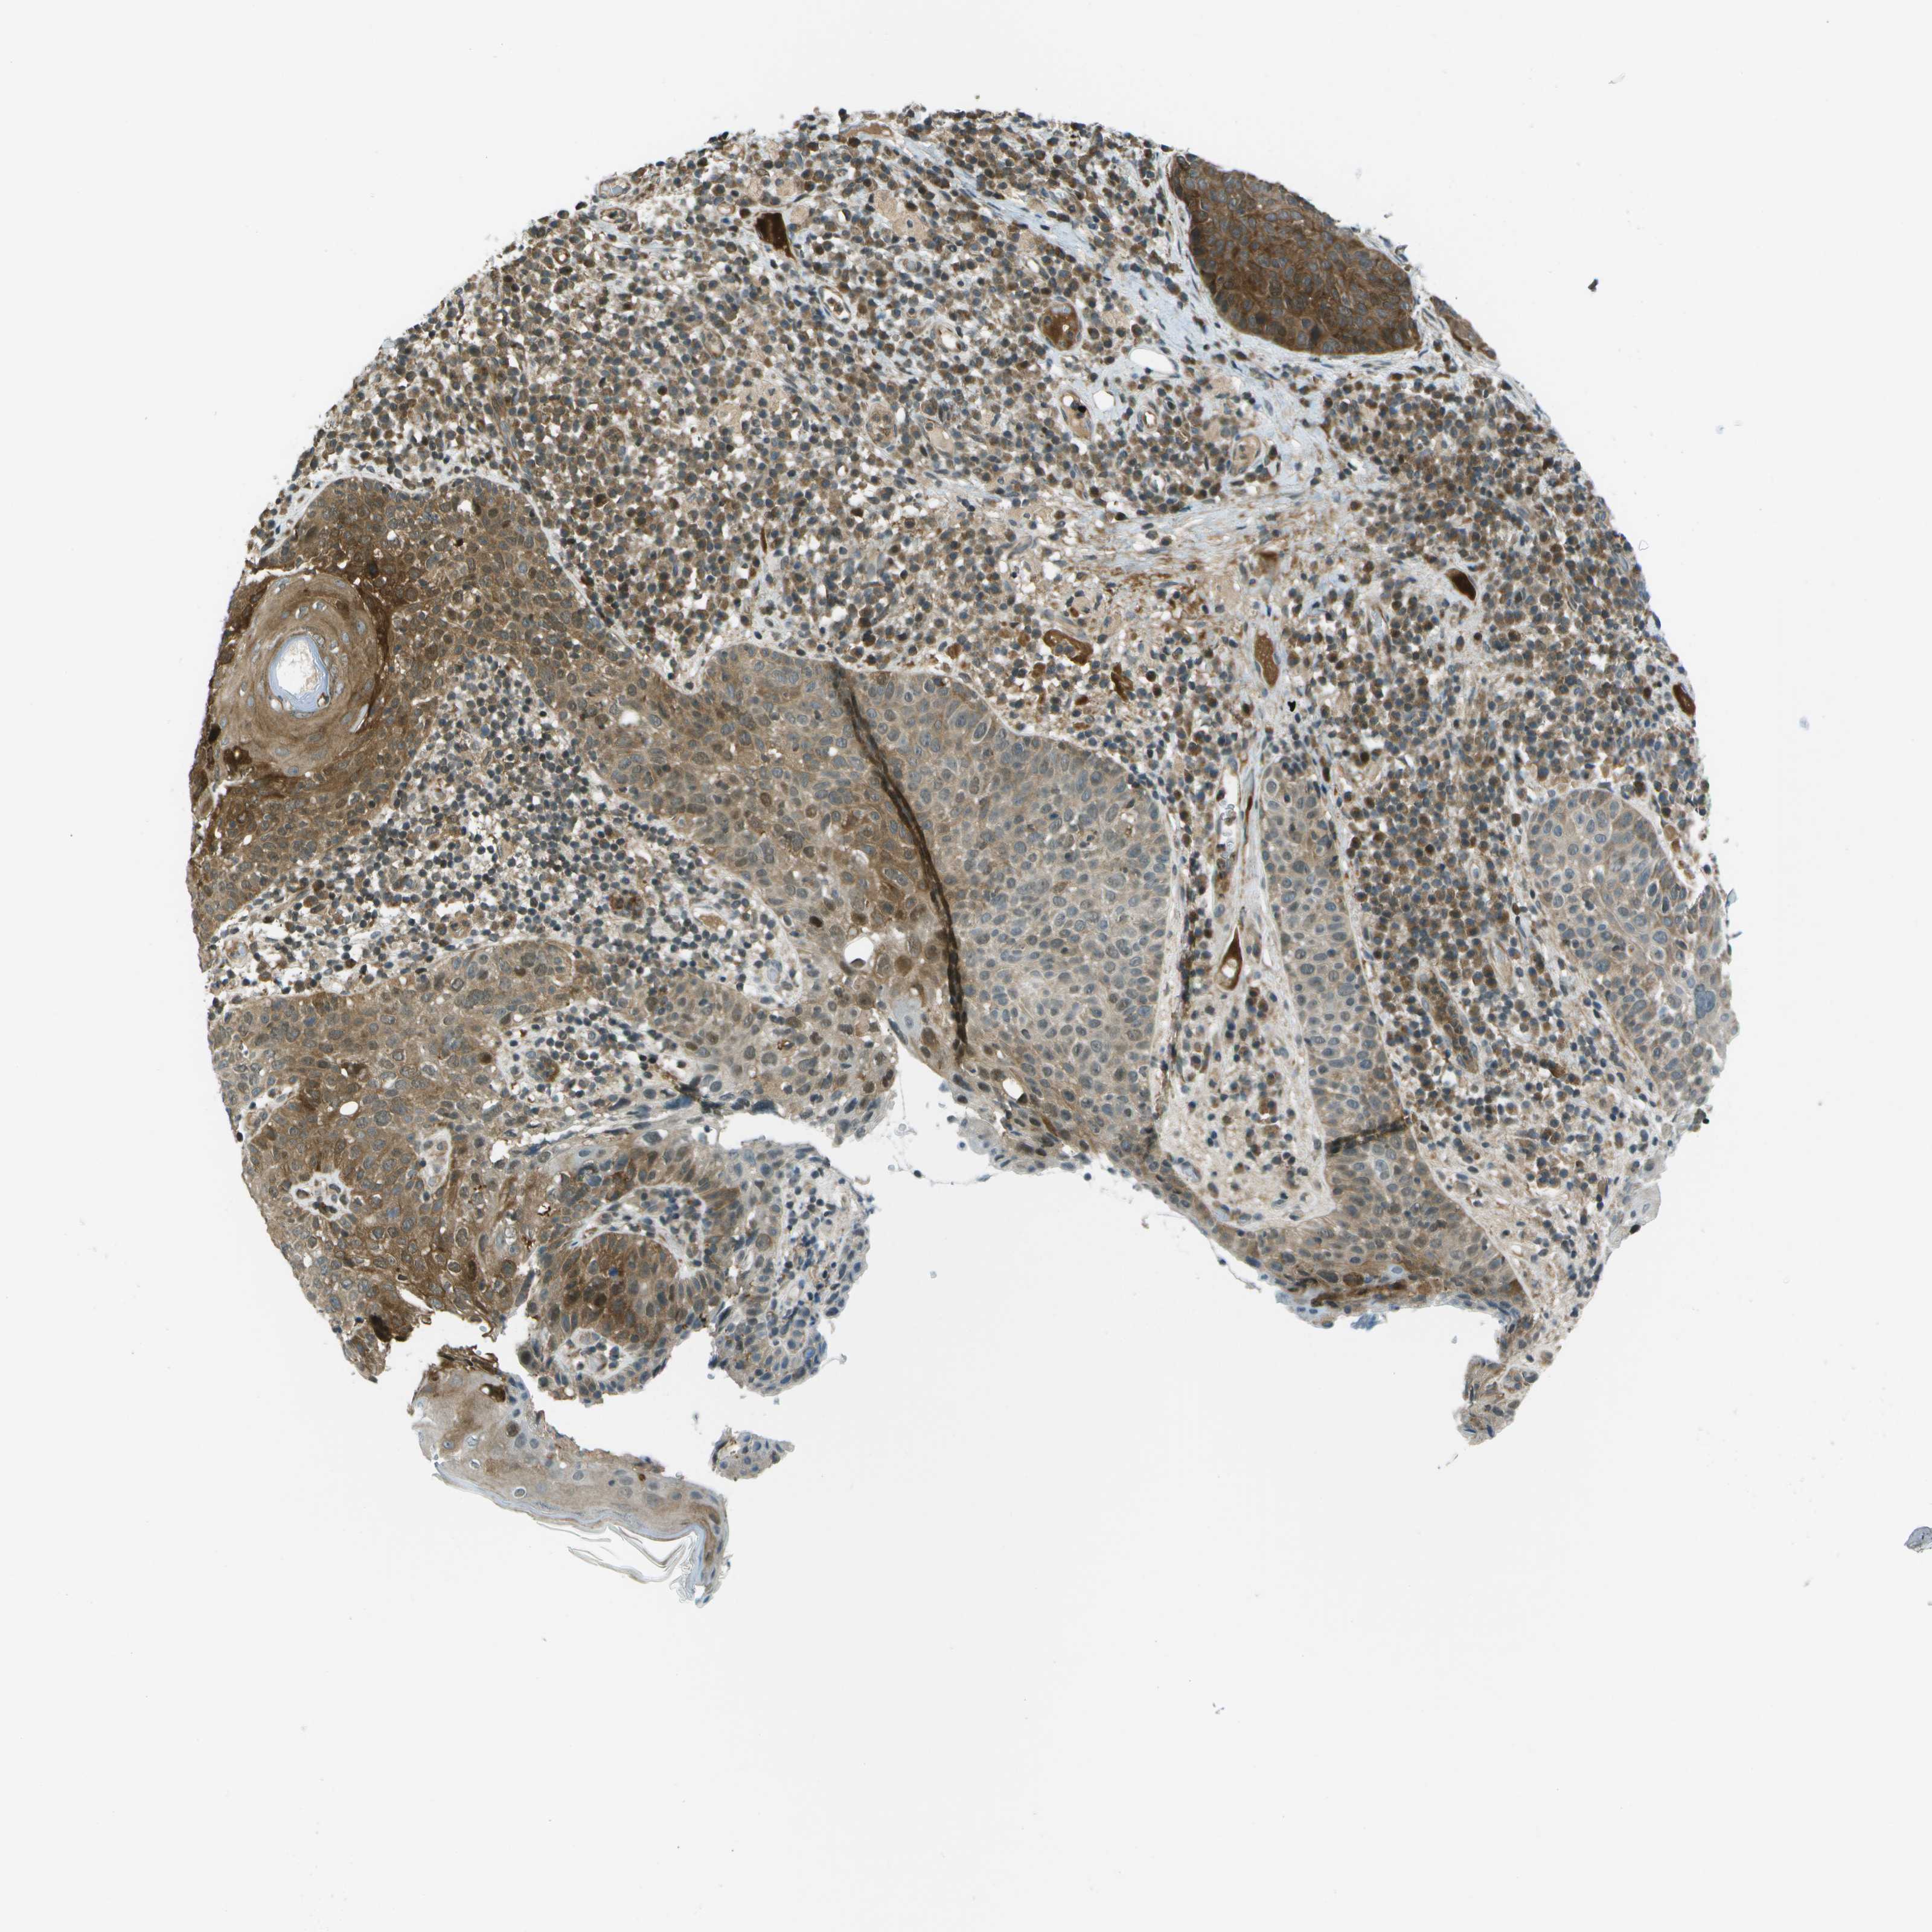

SKIN CANCER - Protein expressioni

A mouse-over function shows sample information and annotation data. Click on an image to view it in a full screen mode. Samples can be filtered based on level of antibody staining by selecting one or several of the following categories: high, medium, low and not detected. The assay and annotation is described here.

Each image is clickable and will lead to virtual microscopy that enables deeper exploration of all samples and also displays staining intensity scores, fraction scores and subcellular localization as well as patient and tissue information for each sample.

Antibody HPA016830

Staining

High

Intensity

Strong

Quantity

>75%

Location

Nuclear

Squamous cell carcinoma in situ, NOS

Squamous cell carcinoma, NOS

Squamous cell carcinoma, metastatic, NOS

Basal cell carcinoma

Adnexal tumor, benign